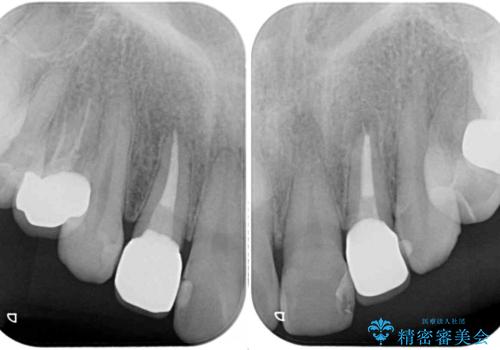

- クラウンから金属の土台が見えてきてしまったとのことで、作り替えを希望して来院された患者様です。

前歯や金属が露出している歯、痛みを感じる歯を中心に、オールセラミッククラウンにて補綴治療することとしました。

以前はセラミッククラウンのフレームとして金属が使用されており、歯肉の経年変化やセラミックのすり減りなどにより、金属が見えるようになってくることがあります。